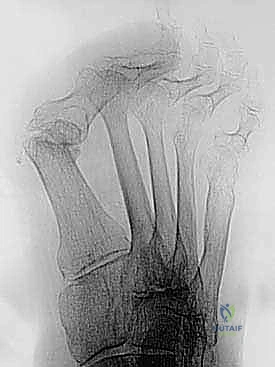

- التصوير بالأشعة السينية (X-rays): صور في وضعية الوقوف (تحمل الوزن) من زوايا متعددة لقياس زوايا التشوه بدقة وحساب مقدار الطول المفقود.

6. التثبيت الداخلي الصلب (Rigid Internal Fixation)

لضمان التئام العظام (وهو ما يستغرق عدة أسابيع)، يجب تثبيت المفصل والطعم العظمي بقوة شديدة. يستخدم الأستاذ الدكتور محمد هطيف أحدث الشرائح المعدنية المصممة خصيصاً لاندماج إبهام القدم (Anatomical Locking Plates) والمسامير التيتانيوم. يتم وضع الشريحة فوق المفصل وتثبيتها بمسامير تمر عبر الطعم العظمي لضمان ثباته المطلق.

7. الإغلاق والتحقق بالأشعة

يتم أخذ صور أشعة سينية داخل غرفة العمليات (Fluoroscopy) للتأكد من المحاذاة المثالية للإصبع، وتصحيح زاوية الارتفاع، والموضع الدقيق للمسامير. بعد ذلك، يتم إغلاق الجرح بخيوط تجميلية ووضع ضمادات معقمة وجبيرة واقية.